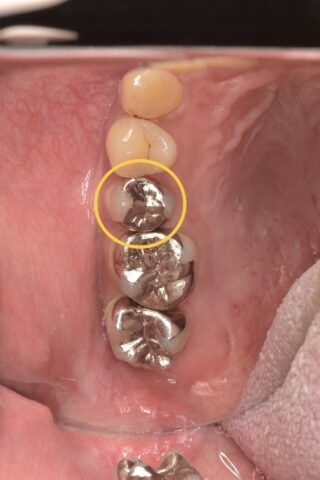

まずはパノラマ写真と口腔内写真をご覧下さい。

今回の部位は右上5番です

元々は金属の詰め物が入っていました。